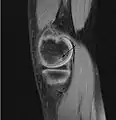

Magnetic resonance imaging (MRI) is useful for staging OCD lesions, evaluating the integrity of the joint surface, and distinguishing normal variants of bone formation from OCD by showing bone and cartilage edema in the area of the irregularity. MRI provides information regarding features of the articular cartilage and bone under the cartilage, including edema, fractures, fluid interfaces, articular surface integrity, and fragment displacement.[37][38] A low T1 and high T2 signal at the fragment interface is seen in active lesions. This indicates an unstable lesion or recent microfractures.[30] While MRI and arthroscopy have a close correlation, X-ray films tend to be less inductive of similar MRI results.[38]

Computed tomography (CT) scans and Technetium-99m bone scans are also sometimes used to monitor the progress of treatment. Unlike plain radiographs (X-rays), CT scans and MRI scans can show the exact location and extent of the lesion.[39] Technetium bone scans can detect regional blood flow and the amount of osseous uptake. Both of these seem to be closely correlated to the potential for healing in the fragment.[40][41]